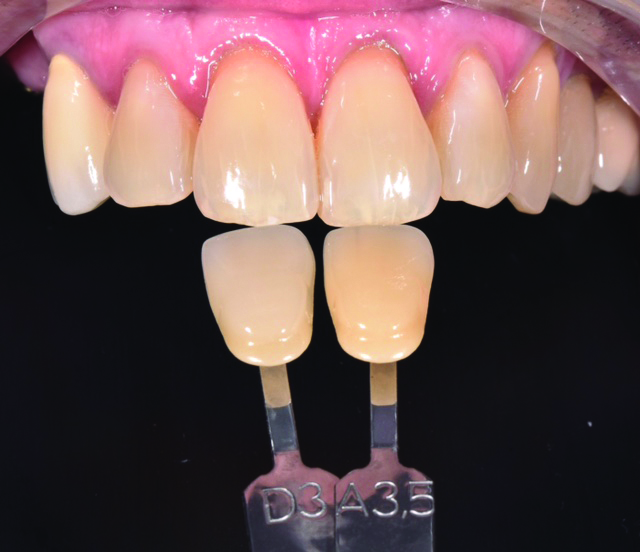

The patient presented 4 months later to begin the restorative phase of treatment. Using the Planmeca EmeraldTM Intraoral Scanner (Planmeca; planmecausa.com), the maxillary and mandibular arches—as well as two buccal bite registrations—were scanned for digital impressions. The Planmeca Emerald Intraoral Scanner easily and accurately captured the dentition within a few minutes. Using the “time saver” feature, the healing abutments were digitally erased from the maxillary arch scan to be used for the implant impression. Elos Accurate Scanbodies (Elos Medtech Dental; elosdental.com) were placed and full seating was confirmed via a periapical radiograph. The scanbodies were then scanned using the Planmeca Emerald Intraoral Scanner to capture the exact position, angle, and rotation of the dental implants (Figure 2 and Figure 3). Following completion of the intraoral scan, the scanbodies were removed and replaced with the healing abutments. The case was photographed, and a custom shade was taken by the dental technician using the VITA classical Shade Guide (Figure 4).

Fig 4. High-resolution photograph with shade tabs to communicate shade.

Figure 4